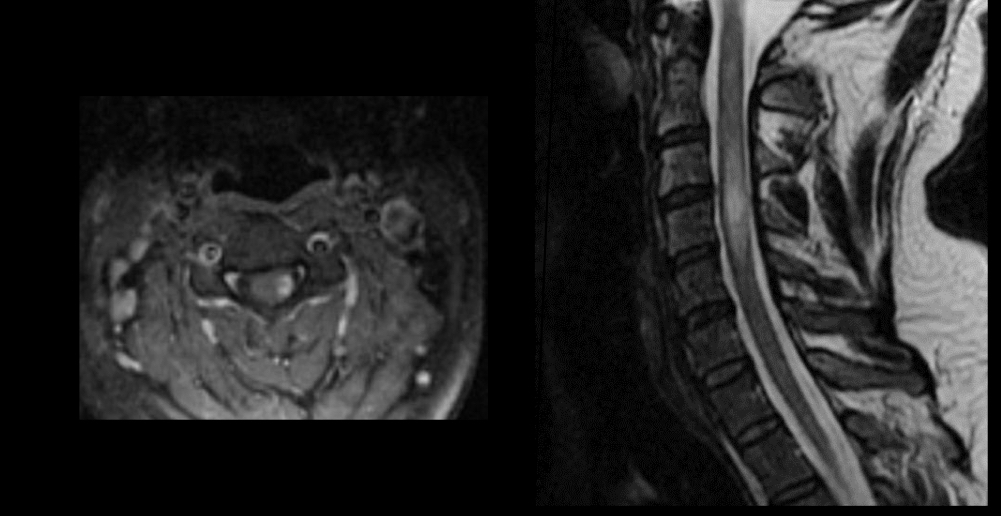

q ves en imagen

A

hiperintensidades calloseptales en T2 Y FLAIR

Peque, lineales, ovoide

Periventriculares

Dedos dawson

en q plano ves DEDOS DAWSON EXAMEN

Plano sagital

involucra a la medula esta enf

yes queen